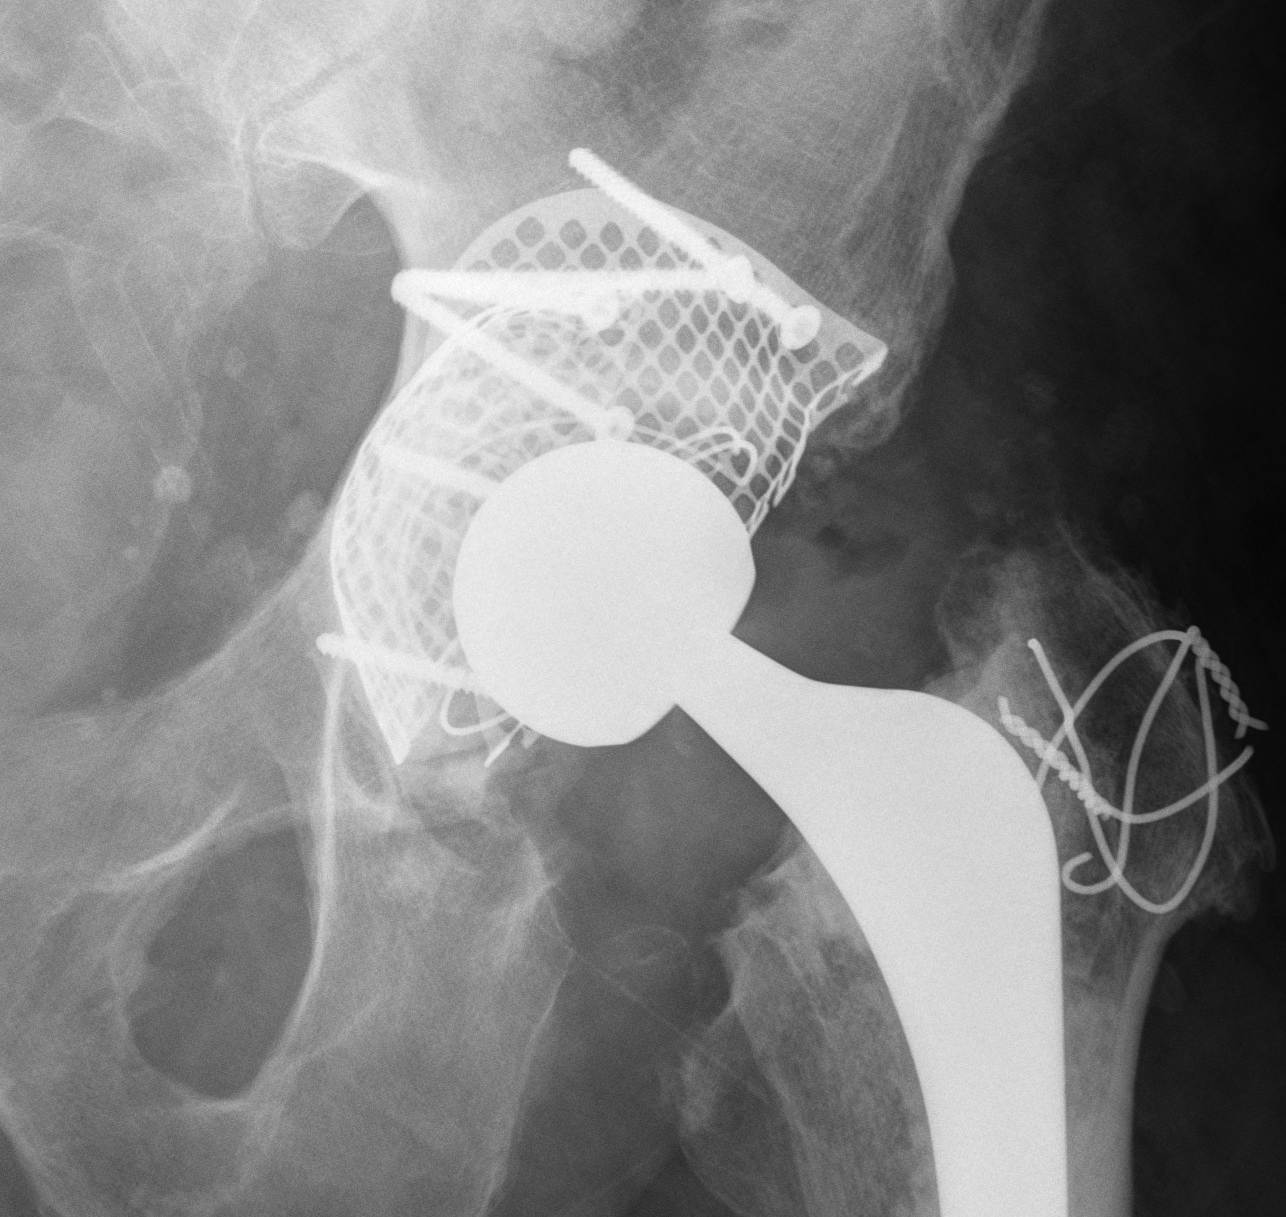

Option: Custom-made triflange components

CT guided model of pelvis

- custom made acetabular cage

- fits defect exactly

- flanges perfectly designed and not malleable to improve strength

- HA coated

- cement poly cup into it

Indications

- massive defects

Results

- 90% 4.5 year survival in complicated patients